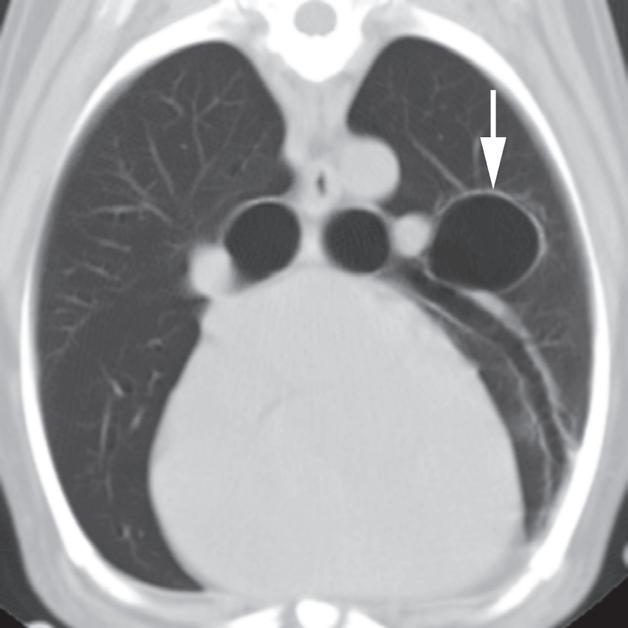

Rycina 4.6.3. Pęcherze płucne (pies) TK

Badanie wykonano u 13-letniego foksteriera z pojedynczym gruczolakorakiem płuc (nie ukazano na rycinie).

Reprezentatywne obrazy TK środkowej i doogonowej części klatki piersiowej, uporządkowane od strony doczaszkowej do doogonowej, ujawniły liczne cienkościenne pęcherze o różnej wielkości. Pęcherze były kuliste i odróżniały się od rurowatego kształtu dróg oddechowych podczas oglądania kolejnych obrazów. Miały również większą średnicę, niż można by oczekiwać w przypadku dróg oddechowych na obwodzie płuca (a–c – duże strzałki). W przeciwieństwie do pęcherzy, drogi oddechowe się rozgałęziały (c – grot strzałki) i towarzyszyły im tętnice oraz żyły płucne (b, c – małe strzałki). U tego pacjenta pęcherze nie powodowały żadnych objawów klinicznych i uznano je za rozwojowe. Ocena makroskopowa i mikroskopowa zmian z usuniętego podczas lobektomii płuca potwierdziła rozpoznanie obrazowe